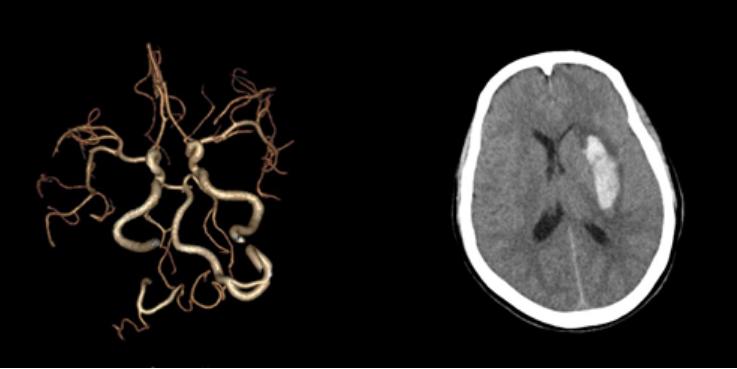

十八、脑出血合并开窗畸形

病例35:右侧额叶急性脑出血合并左侧大脑中动脉M2段开窗畸形

病例36:左侧基底节区急性脑出血合并左侧椎动脉开窗畸形